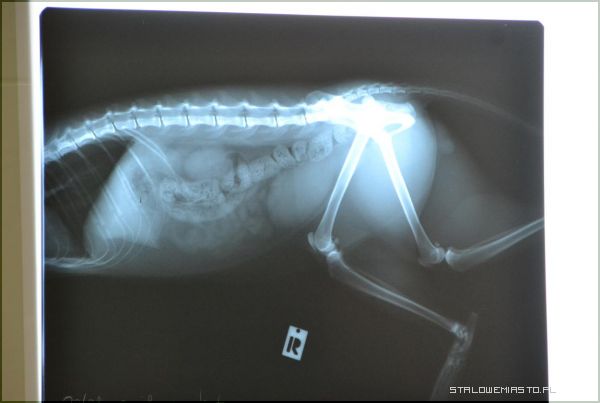

W środę 3 października uczniowie z Klubu Przyjaciół Futrzaka odwiedzili lecznicę dla zwierząt, gdzie spotkali się z lek. weterynarii Maciejem Oręziakiem. Dzieci poznały wyposażenie gabinetu weterynarza, sprzęt i narzędzia jakie stosuje się podczas różnych zabiegów. Duże zainteresowanie wywołały różne urządzenia, m.in. rentgen. Lekarz Oręziak pokazywał zdjęcia obrazujące przypadki złamań oraz obrazy tego samego zwierzęcia po operacji czy zabiegu.